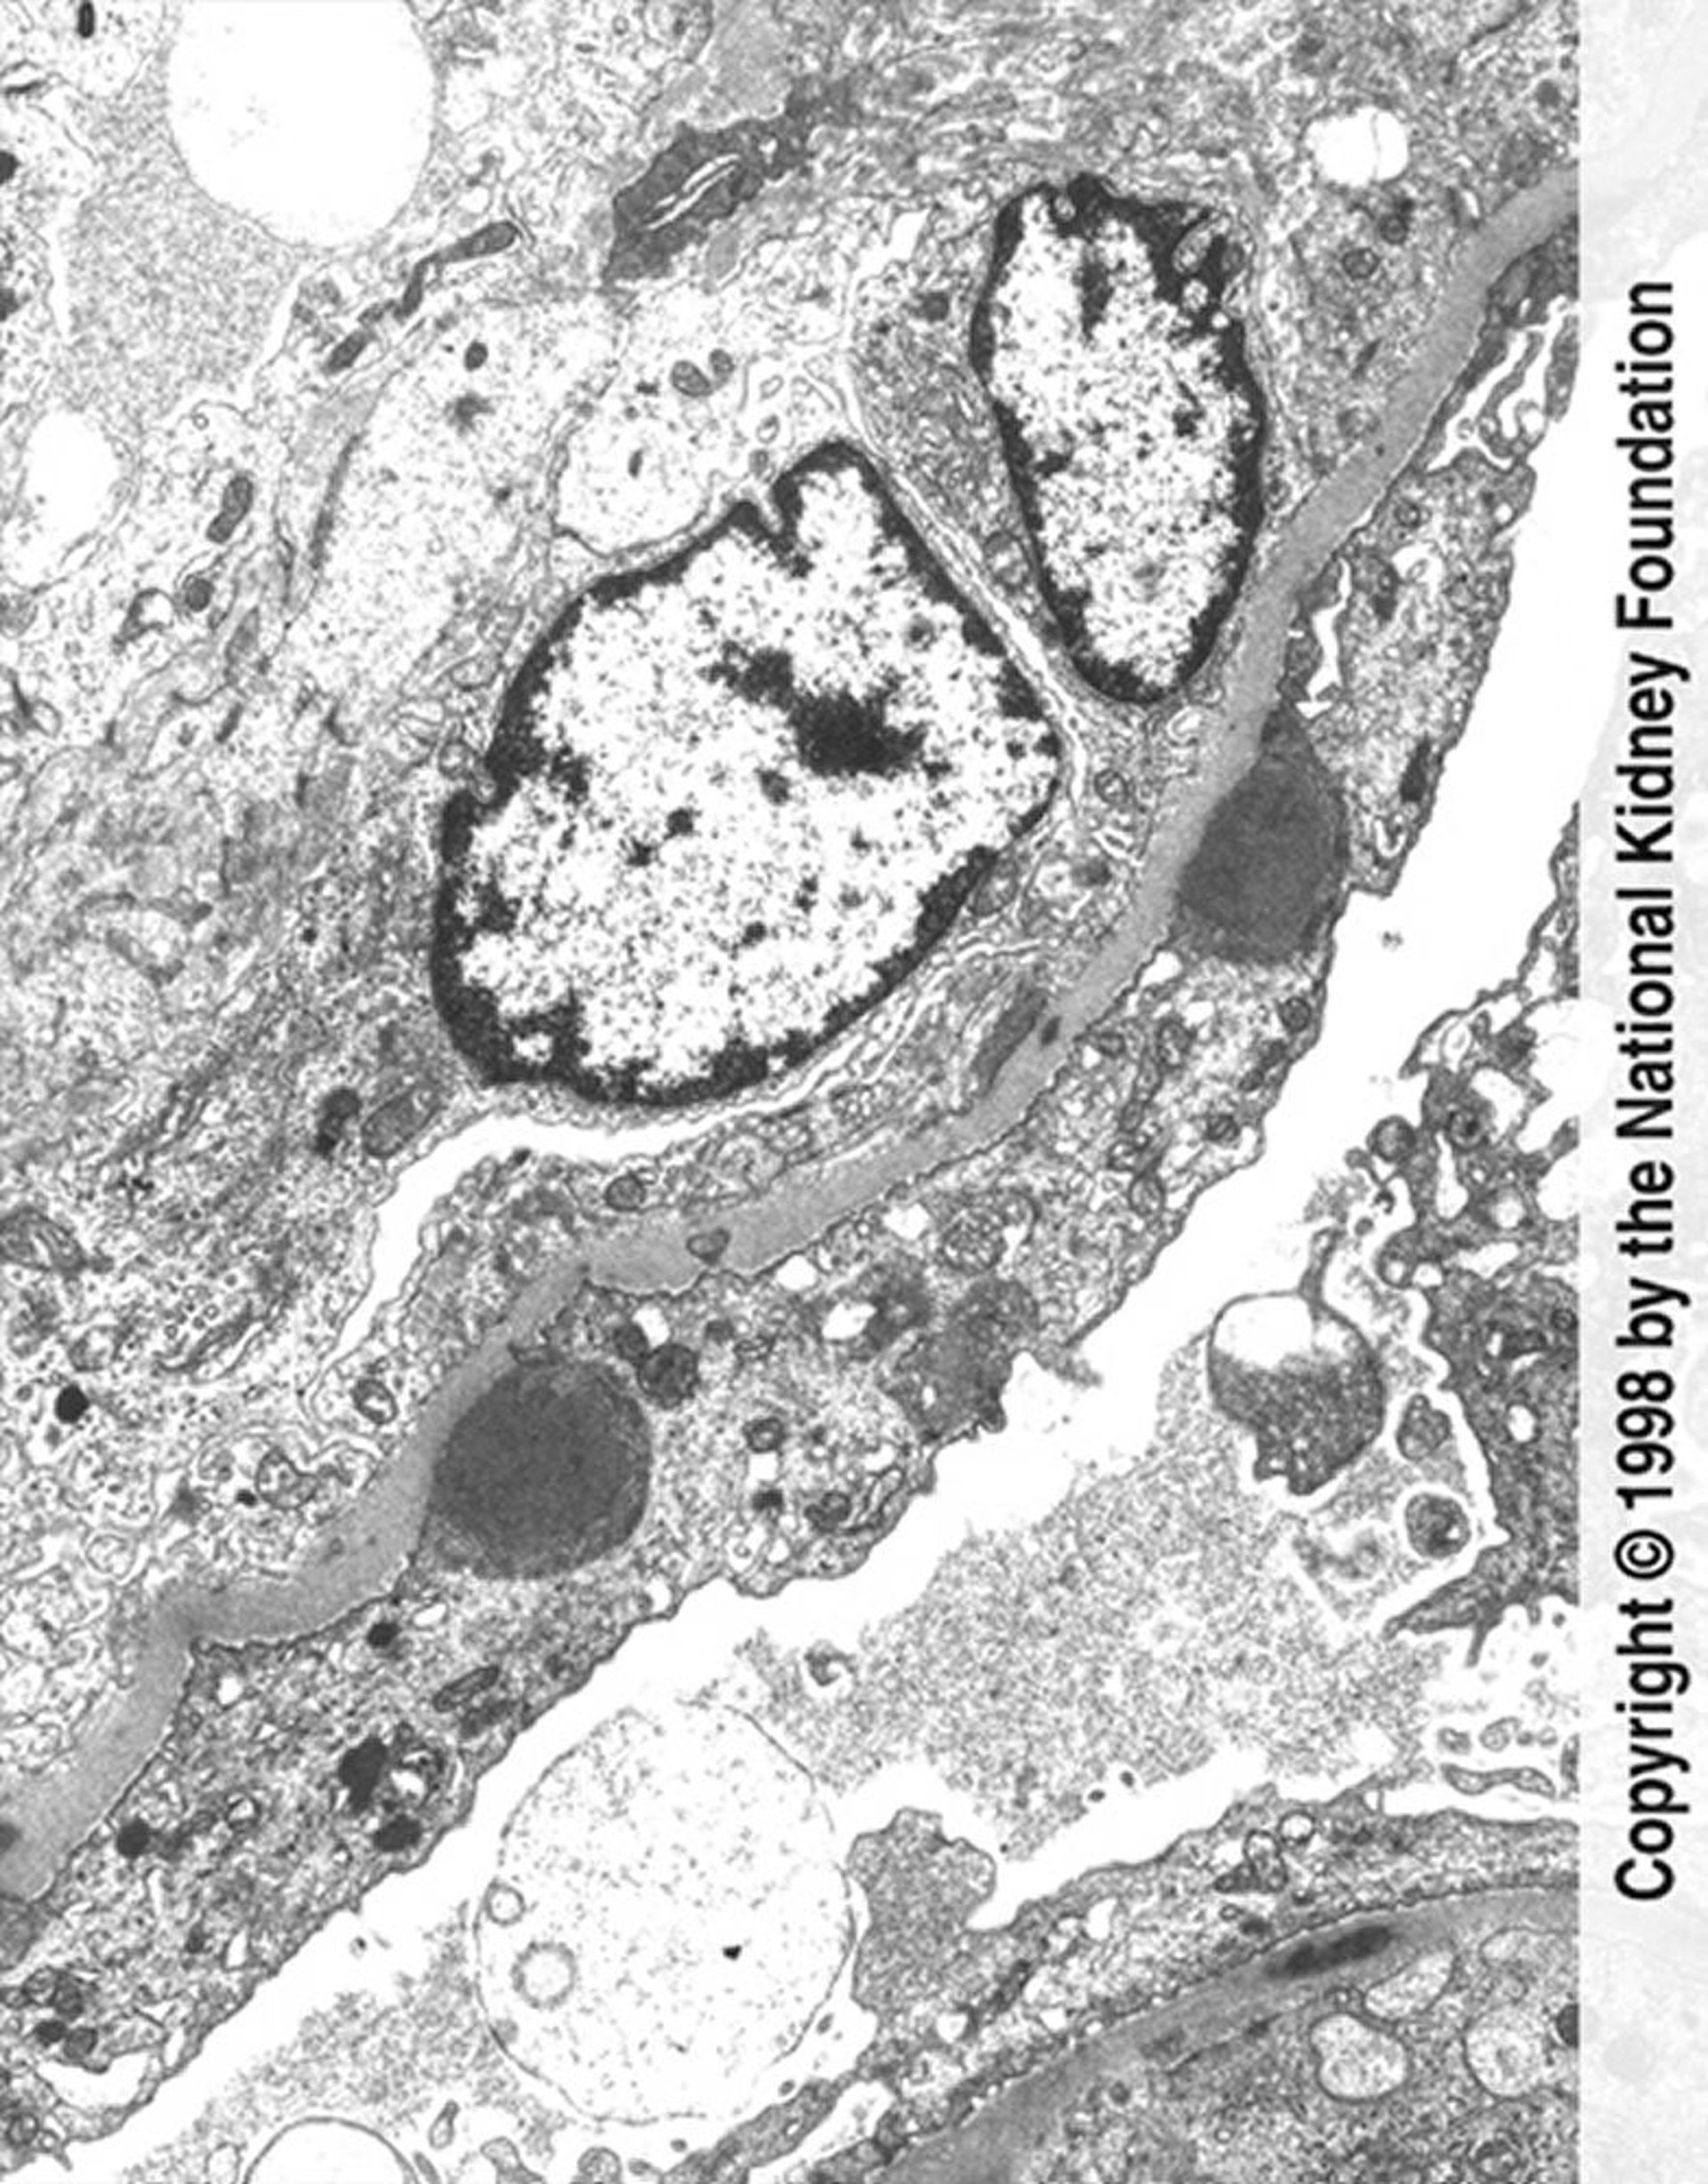

Glomérulonéphrite post-infectieuse (dépôts de complexes immuns)

Des dépôts de complexes immuns en forme de bosse (gris foncé) avec un effacement important des pédicelles et une prolifération endocapillaire sont visibles sur la micrographie électronique à transmission (×11 250).

Image fournie par Agnes Fogo, MD, and the American Journal of Kidney Diseases' Atlas of Renal Pathology (voir www.ajkd.org).